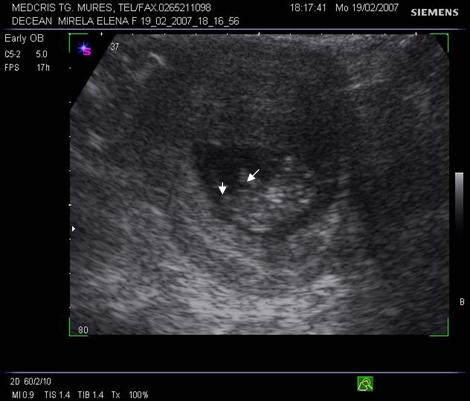

Fig. nr. 14. Sarcina 7 sapt( sageata indica embrionul )